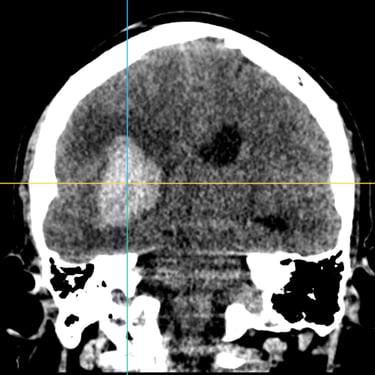

Hemorragia Intracerebral: Craneotomía y Evacuación del Hematoma

La hemorragia intracerebral es una emergencia neurológica grave que requiere diagnóstico rápido y tratamiento oportuno. Cuando el hematoma produce efecto de masa, deterioro del estado de conciencia o riesgo de herniación, la craneotomía y evacuación quirúrgica se convierten en la opción indicada. Este procedimiento permite abrir la bóveda craneal, retirar el coágulo y disminuir la presión intracraneal, preservando la función neurológica. Su objetivo es detener el daño secundario, mejorar la perfusión cerebral y estabilizar al paciente. La intervención temprana, combinada con cuidados críticos especializados, aumenta las posibilidades de supervivencia y recuperación funcional en este tipo de emergencia.